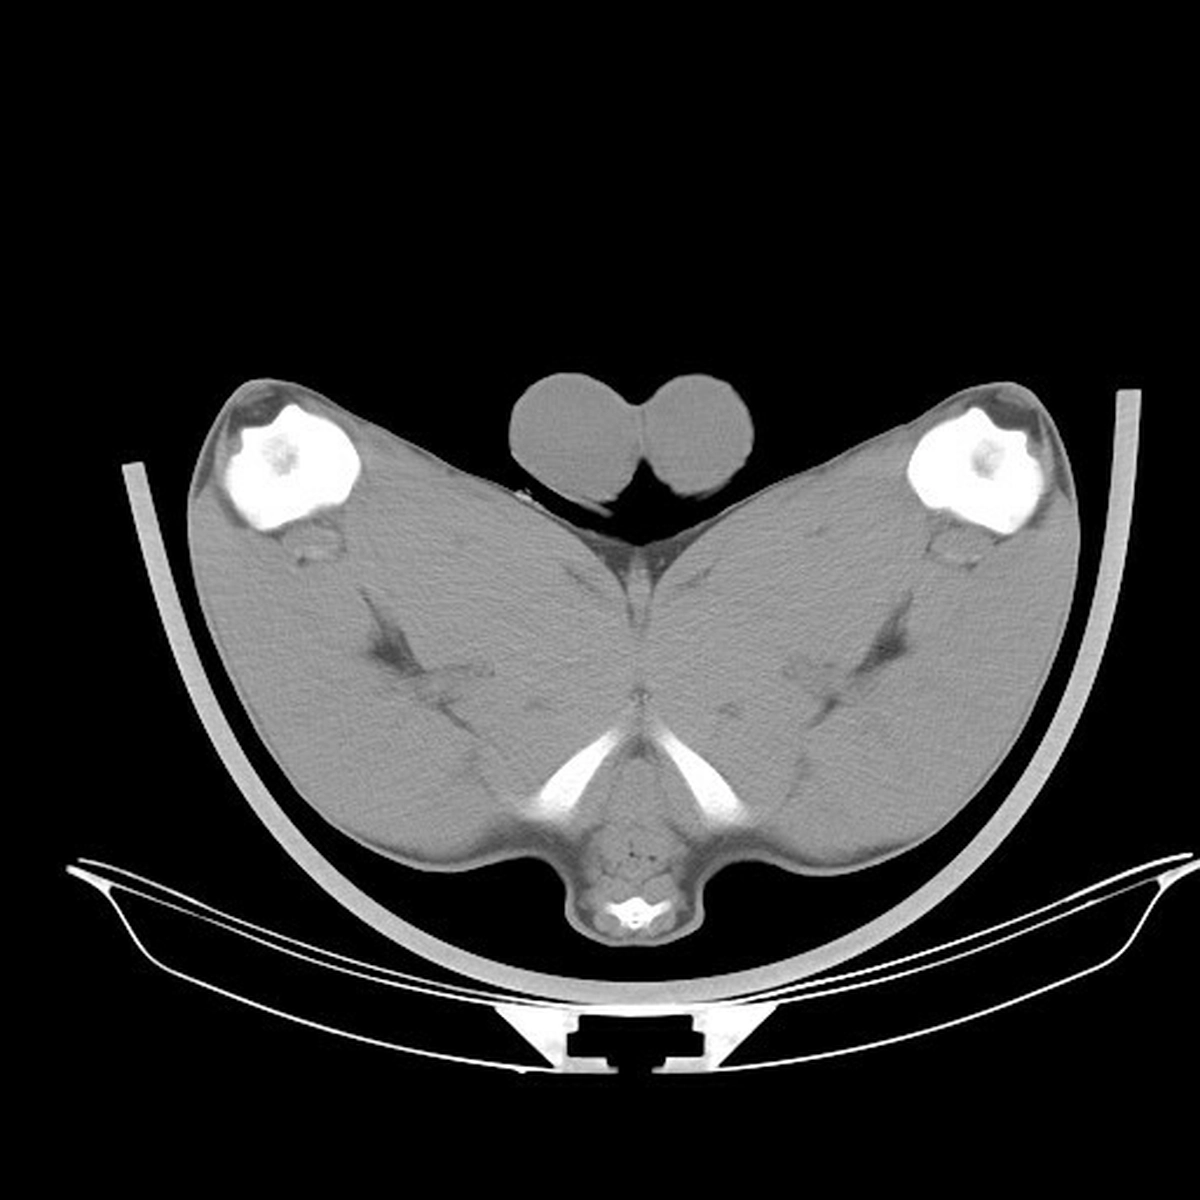

QMS Head of Industry Development, Bruce McConachie says: "Used in both humans and animals, CT scanning is a diagnostic process, completely safe for animals. The CT scanning machine mimics a carcase grader used in abattoirs, measuring the diameter of certain muscles at fixed points around the carcase, calculating muscle dimensions, muscle volume, bone density, internal fat, spine length and pelvic dimensions. An x-ray tube moves slowly around the animal, taking cross sectional images of the entire body. These images allow specific anatomical locations and measurements to be recorded as key performance traits, which can aid breeders’ decision-making process when selecting sheep, particularly rams. These measurements can help to predict the final carcase performance of that animal, and therefore forecast that animal’s expected progeny profile and performance. The resulting measurements inform the key traits for terminal breeding stock being sold within the industry.